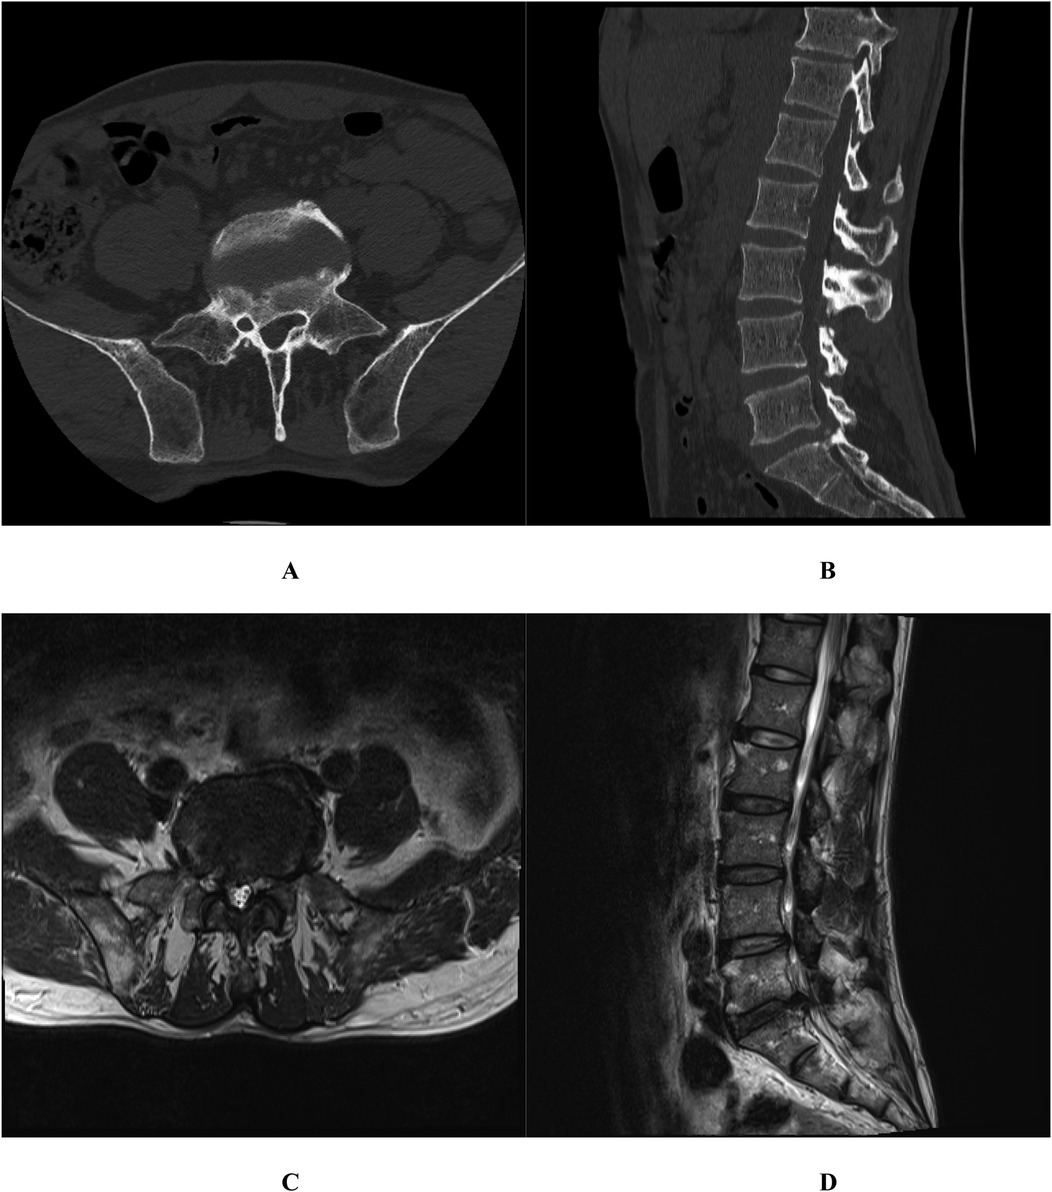

Posterior marginal osteophytes at the vertebral level are frequently observed in individuals with lumbar disc herniation (LDH); however, complete encasement of the nerve root by such osteophytes is exceedingly uncommon. We present two cases of surgical management of vertebral posterior marginal osteophytes completely encasing the nerve root. This report examined two cases of LDH accompanied by vertebral posterior marginal osteophytes completely encasing the nerve roots. Both patients underwent spinal canal decompression, discectomy, and intervertebral fusion. Postoperatively, varying degrees of nerve root injury were noted. By the 3-month follow-up, marked recovery in neurological function was achieved in both cases. The presence of vertebral posterior marginal osteophytes completely encasing the nerve root represents a notable risk factor for nerve root injury in LDH cases. Tailored surgical approaches are imperative to minimize complications and optimize patient outcomes.